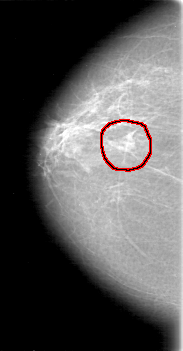

D_4081_1.RIGHT_CC

RIGHT_CC LINES 5251 PIXELS_PER_LINE 2731 BITS_PER_PIXEL 12 RESOLUTION 43.5 OVERLAY

FILE: D_4081_1.RIGHT_MLO.OVERLAY

TOTAL_ABNORMALITIES 1

ABNORMALITY 1

LESION_TYPE MASS SHAPE IRREGULAR MARGINS OBSCURED

ASSESSMENT 0

SUBTLETY 5

PATHOLOGY BENIGN

TOTAL_OUTLINES 1

BOUNDARY